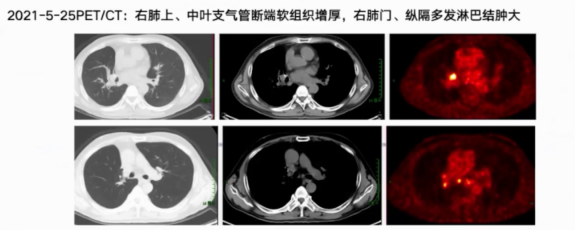

2021年5月复查CT发现右肺中叶残端较前饱满,PET/CT提示右肺上中叶支气管断端软组织增厚伴代谢增高,右肺门和纵隔淋巴结肿大伴代谢增高,考虑复发转移。